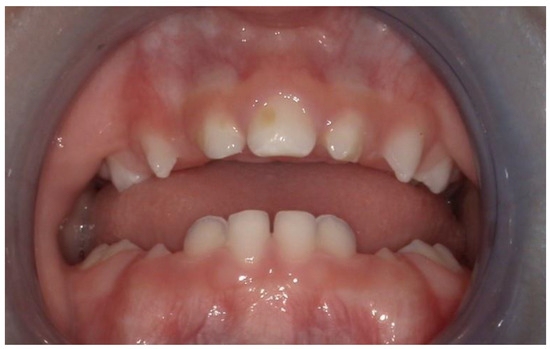

We present the rare case of an infant with HPE and CNPAS complicated by acute respiratory failure. The concomitant presence of an SMMCI was treated using a combined otorynolaringological–orthodontic approach. The multidisciplinary minimally invasive treatment involved a team comprising a neonatologist, a geneticist, a pneumologist, an ENT (ear, nose, and throat) doctor, and a pediatric dentist. The following is a detailed description of the events, the therapeutic path, and the long-term follow-up of the patient. An 8-day-old girl was admitted to the Neonatal Intensive Care Unit (TIN) of the Bambino Gesù Children’s Hospital (Rome, Italy). The baby was born at 39 weeks by caesarean section, with a birth weight of 2820 g and a length of 47.3 cm. The Apgar score was 8/10. During the clinical examination at birth, the following clinical signs were observed: cutaneous syndactyly of the II-III toes bilaterally, hypotelorism, low weight, and short stature. Respiratory distress and cyanosis ensued after a few hours. The patient was ventilated with neo-puff without much benefit. The infant was then administered CPAP (continuous positive airway pressure) and was intubated on the second day of life due to the worsening of her overall condition. Brain and facial mass MRI (magnetic resonance imaging) were performed at the birth hospital, revealing a congenital nasal pyriform aperture stenosis and the presence of a solitary median maxillary central incisor. On the eighth day of life, the patient was referred to the Bambino Gesù Children’s Research Hospital where she underwent the following tests: abdominal ultrasound, eye examination with negative results, GH, FSH, LH, cortisol, thyroid hormones, and ACTH levels, the results of which were all in the normal range. The infant also underwent an echocardiogram, which showed evidence of pervious foramen ovale. After evaluation at the Medical Genetics Department, molecular analysis showed a heterozygous variant of the GLI2 gene, for holoprosencephaly, which is classified as a class IV variant arising de novo, and which was absent in the DNA extracted from the blood of the parents. Pathogenetic variants of the GLI2 gene are associated with an autosomal dominant form of holoprosencephaly (HOLOPROSENCEPHALY 9; OMIM # 610829) with variable phenotypic expression and, in some cases, incomplete penetrance [14]. The infant was then evaluated by the ENT doctor, who performed a nasal endoscopy using a flexible laryngoscope under general anesthesia, which revealed the presence of mesenchymal bridges obstructing the right nasal cavity and a left-convex dislocation of the nasal septum. After this evaluation, the ENT doctor decided to proceed with the lysis of mesenchymal bridges, and subsequently a gentle dilation of the nasal cavities (Hegar of increasing caliber up to 4) was performed. After the widening of the nasal cavities, stabilization was achieved through balloon dilation, and two trans-nasal stents with small calibers (2.5 in one nasal cavity and 3 in the other) were placed. The infant was simultaneously evaluated by a pediatric dentist who specialized in orthodontics. The dentist found evidence of the following clinical signs: the palate had a markedly ogival shape, with growth in the direction of the anterior vertex; the median raphe palatine was severely depressed; and there was a reduction in the transverse diameters of the upper jaw. In the operating room, the dental team took an impression of the palate with addition silicone in order to create an intraoral device (Figure 1). After the surgery, given the presence of the characteristic palatal deformity, a decision was made to increase the respiratory space by applying a device. On the same day, a neonatal palatal expander plate (NPEP) [13] was built by a dental technician and positioned in the upper arch (Figure 2). The device was a mucous anchoring plate made of acrylic resin, which was extended buccally with flanges to ensure good retention [13]. A screw was placed at the center of device, to correspond with the palate median suture. To avoid any risk of suffocation, the team inserted a safety wire through two holes in the canine region. The safety wire was a surgical silk suture thread (without a needle) of approximately 70 cm in length. The orthopedic maxillary expansion therapy was initiated in order to favor the distraction of the palate at the level of the median palatine suture and assist the nasal dilation. A precise protocol for the use of the orthodontic device was established, and the child responded very well. The saturation and frequency remained regular during the insertion maneuvers, and the child kept the device in her mouth throughout the procedure. We recommend activating the central screw of the device 24 h after insertion (Figure 3). In this case, for the first day, the infant wore the device for two hours, three times a day. On the subsequent days, the device was worn for three hours, three times a day, under the constant supervision of the parents or caregivers. Immediately after the insertion of the device, the patient started swallowing and sucking normally, demonstrating that the physiological sucking–swallowing mechanism had been activated. Five days after surgery, the stents were removed and the girl was able to breath on her own, with a few episodes of desaturation that spontaneously resolved. Subsequently, the clinical condition of the child remained stable, and the follow-up visits with the ENT specialists and the orthodontist showed positive results: she resumed spontaneous breathing with good saturation (97%), her bottle feeding was going well and she had gained weight, and a valid nasal respiratory space had been secured, which was associated with the rosy appearance of the soft tissues of the oral cavity. After 15 days, the use of the expansion device was suspended and the patient was discharged. The patient underwent follow-up visits once a month for the first six months and thereafter every six months for the monitoring of respiratory function and airway patency, dental eruption, the stability and health of the median maxillary central incisor, and the growth of the jaw complex (Figure 4).

Figure 4. Two-year follow-up: the median maxillary central incisor is healthy and stable.